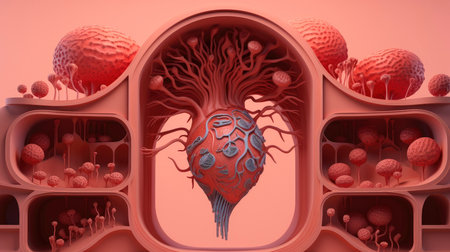

Organic growth of tree branch shows anatomy generated by artificial intelligence